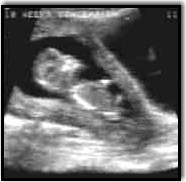

Ultrasonography, commonly called sonography, is a diagnostic medical procedure that uses high frequency sound waves (ultrasound) to produce dynamic visual images of organs, tissues, or blood flow inside the body. This type of procedure is often referred to as a sonogram or ultrasound scan. Ultrasonography can be used to examine many parts of the body, such as the abdomen, breasts, female reproductive system, superficial structures, prostate, heart, and blood vessels.

Ultrasonography is increasingly being used in the detection and diagnosis of heart disease, heart attack, and vascular diseases that can lead to stroke. It is also used to guide a fine needle, for tissue biopsy and amniocentesis, and to assist in taking a sample of cells from an organ or structure for lab testing (for example, a test for cancer in breast tissue and fetal growth in uterus).

A diagnostic medical sonographer is a highly-skilled professional who uses specialized equipment to create images of structures inside the human body that are used by physicians to make a medical diagnosis. The process involves placing a small device called a transducer against the patient's skin near the body area to be imaged. The transducer works like a loudspeaker and microphone because it can transmit sound and receive sound. The transducer sends a stream of high frequency sound waves into the body that bounce off the structures inside. The transducer detects sound waves as they bounce off the internal structures as echoes. Different structures in the body reflect these sound waves differently. These echoes are analyzed by a computer to make a real-time image of the structure(s) on a television screen or that can be recorded on, C-D rom, film, video tape or video paper.